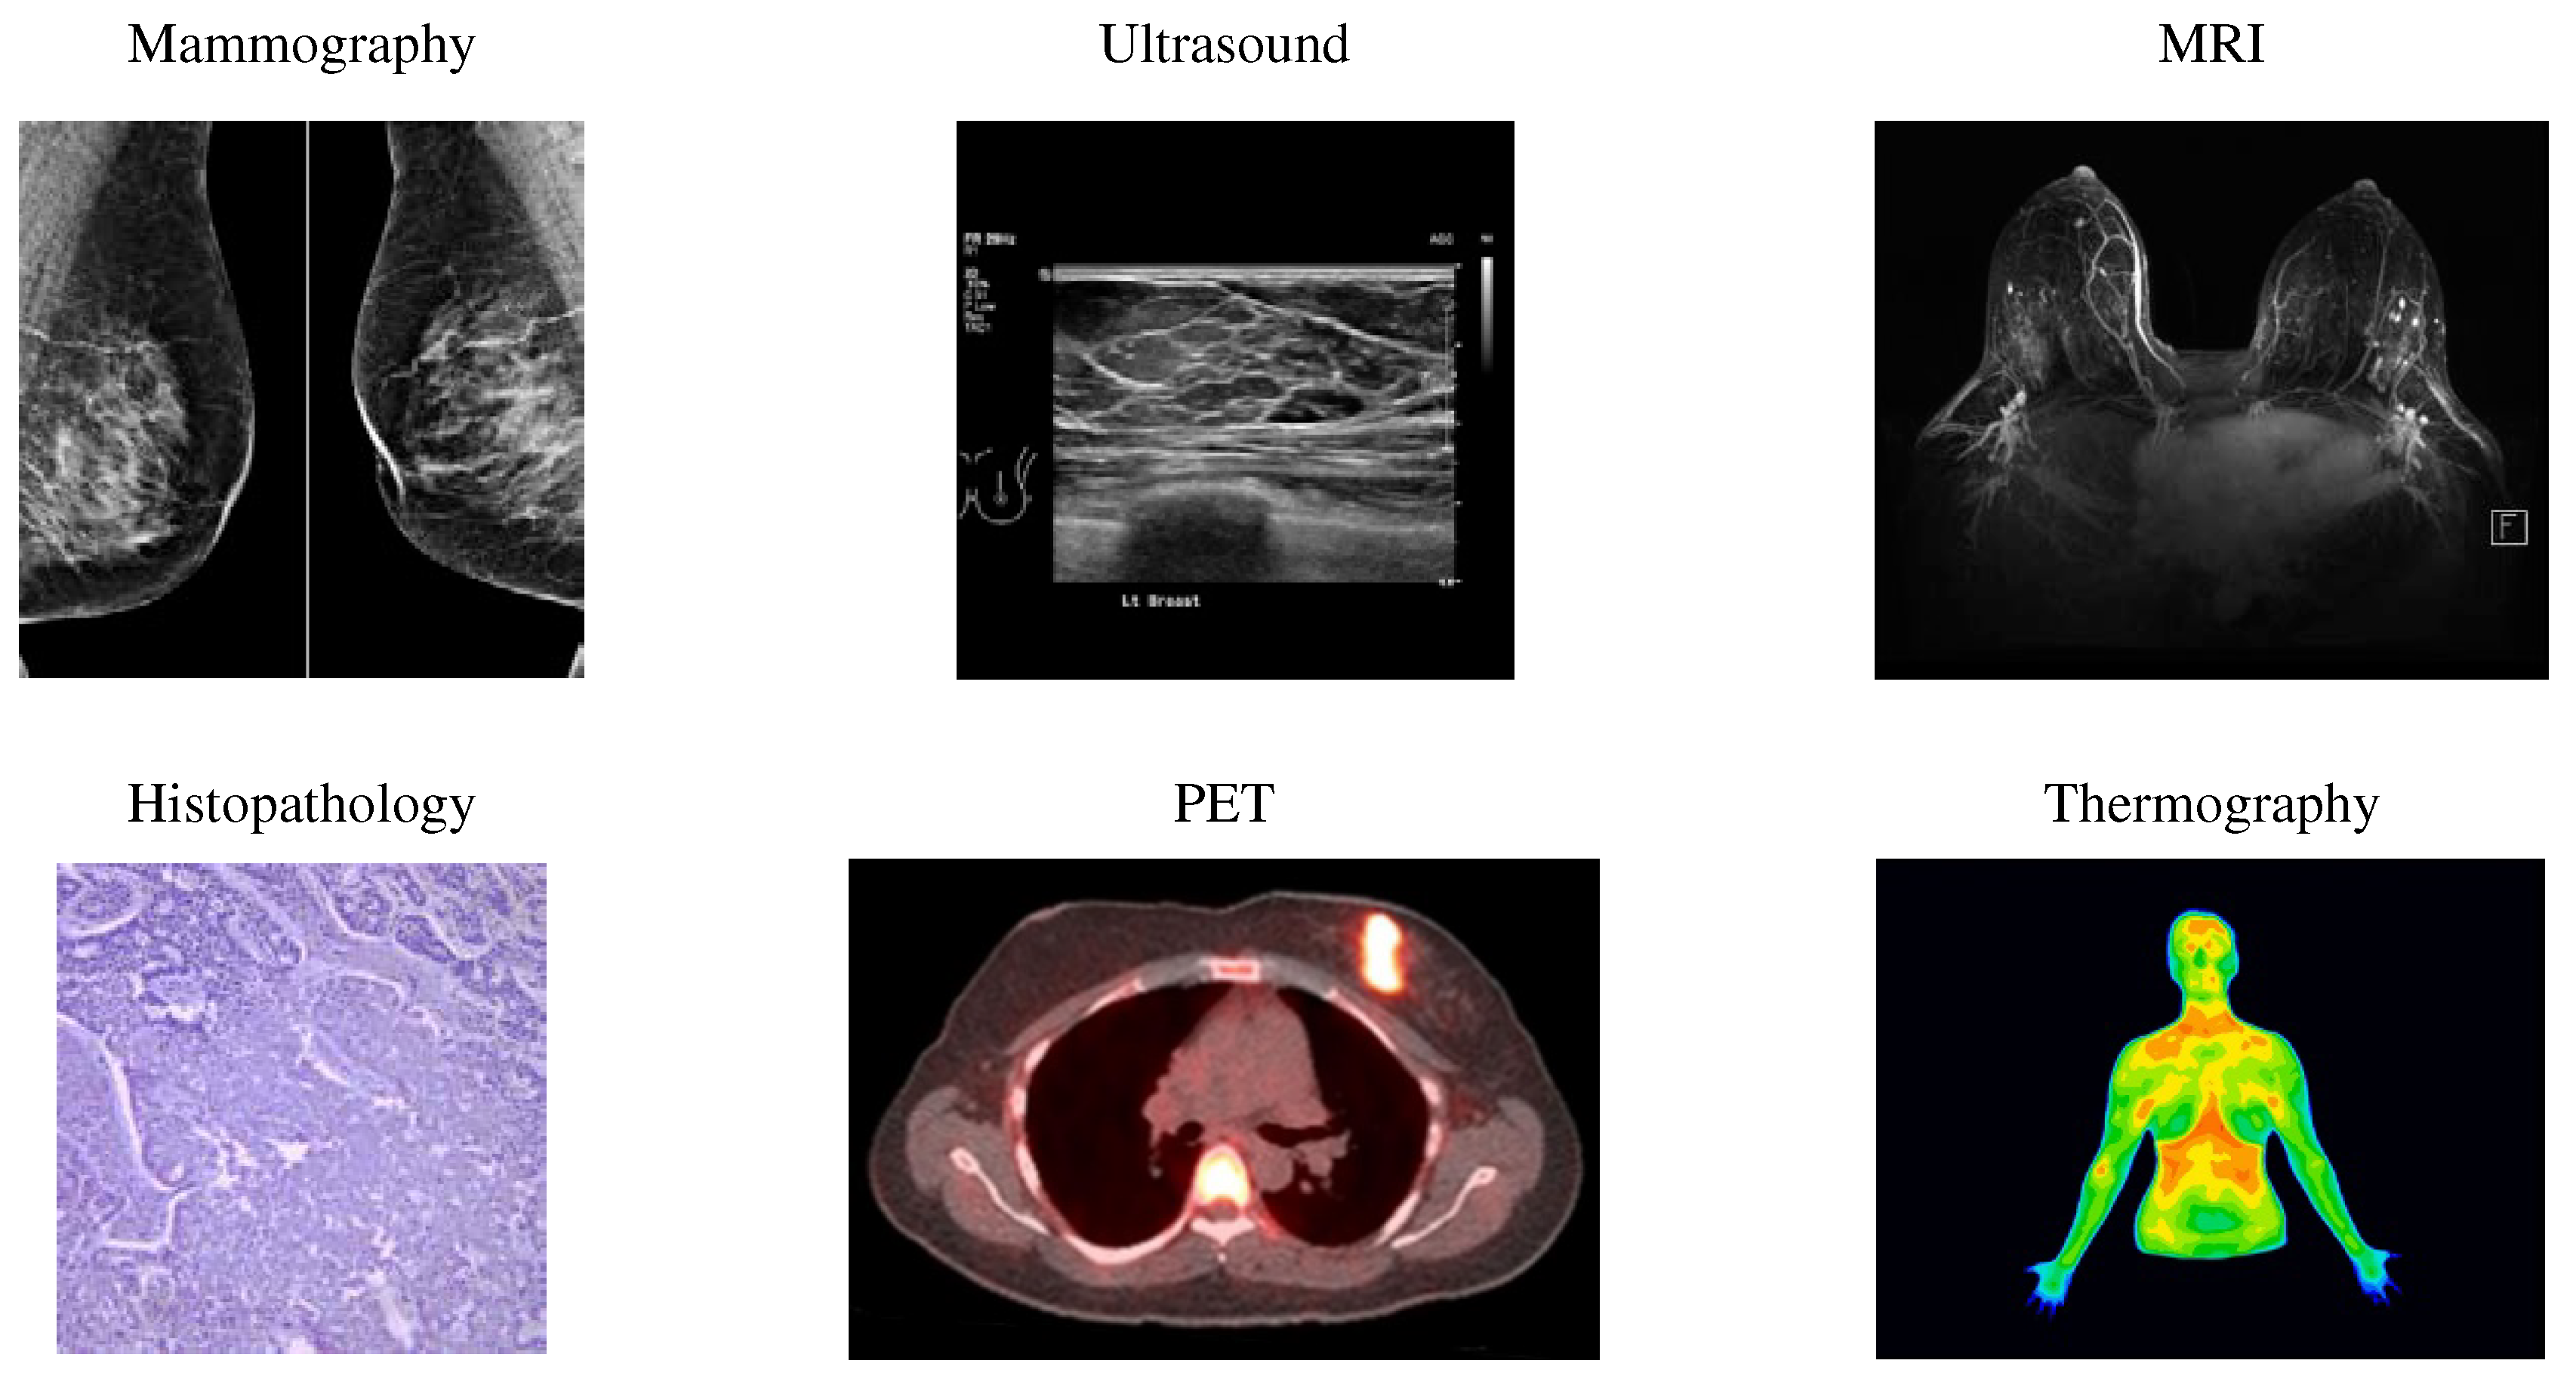

By screening, abnormalities in the breast can detect in the early stages. Screening looks for signs of disease before symptoms appear. Various imaging modalities utilize for breast cancer screening, such as ultrasound, mammography, Positron Emission Tomography (PET), Magnetic Resonance Imaging (MRI), histopathology, and thermography (Figure 1). Table 1 summarizes the benefits and drawbacks of different imaging modalities.

One of the most common breast cancer screening tests is mammography, using uses X-rays to image the breast and can identify and diagnose tiny and unpalpable masses. Mammography can detect abnormal cells around the breast duct, known as Ductal Carcinoma in Situ (DCIS). Factors like the skill and experience of the radiologist, tumor size, and breast tissue density can affect mammography sensitivity. Mammography is unsuitable for dense breasts because both dense tissue and breast abnormalities, such as calcification and tumors, are white in mammography images [9].

Ultrasound is a painless procedure using high-frequency sound waves for black-and-white breast tissue and structure imaging. This imaging detects even the most minor abnormalities in dense breasts and helps to detect a solid mass or fluid-filled cysts that are difficult to see on a mammogram. Furthermore, ultrasound can direct the biopsy operation at the assembly area. Ultrasound is available extensively and relatively easy to perform while not giving radiation to a person. It is also less expensive than other imaging options.

MRI use for women with a higher risk of breast cancer. MRI is a method that uses magnets, a computer, and radio waves to form detailed images of breast tissue. Since X-rays do not operate in this method, the patient will not expose to radiation. MRI can detect some cancers that do not observe on mammograms; it possibly finds things that are not cancer (or false positives).

Histopathology is the microscopic examination of whole tissue samples. A histopathologist can view potentially cancerous or atypical tissues and assist other medical specialists in making diagnoses or assessing the effectiveness of treatments.

In a positron emission tomography scan as an imaging test, a radioactive drug (tracer) searches for the potential spread of breast cancer. Hence, it can recognize areas of cancer possibly not detected by a CT scan or MRI.

One of the natural indicators of breast tissue abnormalities is the temperature change in the cancerous area. Breast thermography is a non-invasive technique that detects early signs of breast cancer regarding blood circulation and body temperature changes. In the breast thermography screening method, infrared rays display a thermal image of the breast tissues.